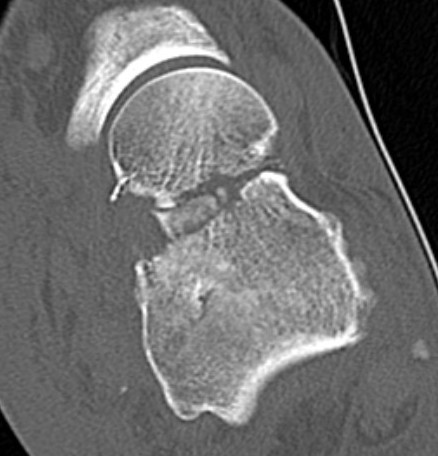

Xray / CT

Ensure no displacement / malalignment

Canale view

- evaluates talar neck

- foot everted 15 deg

- look for medial shortening / varus

Xrays

| AP | Lateral | Canale View |

|---|---|---|

| Entry point of the screws |

Evaluate neck reduction

|

Evaluates the neck reduction |

Lateral off articular surface Medial through articular cartilage |

Depth of screws |

Beam angled 75o to foot Foot 15o pronated |